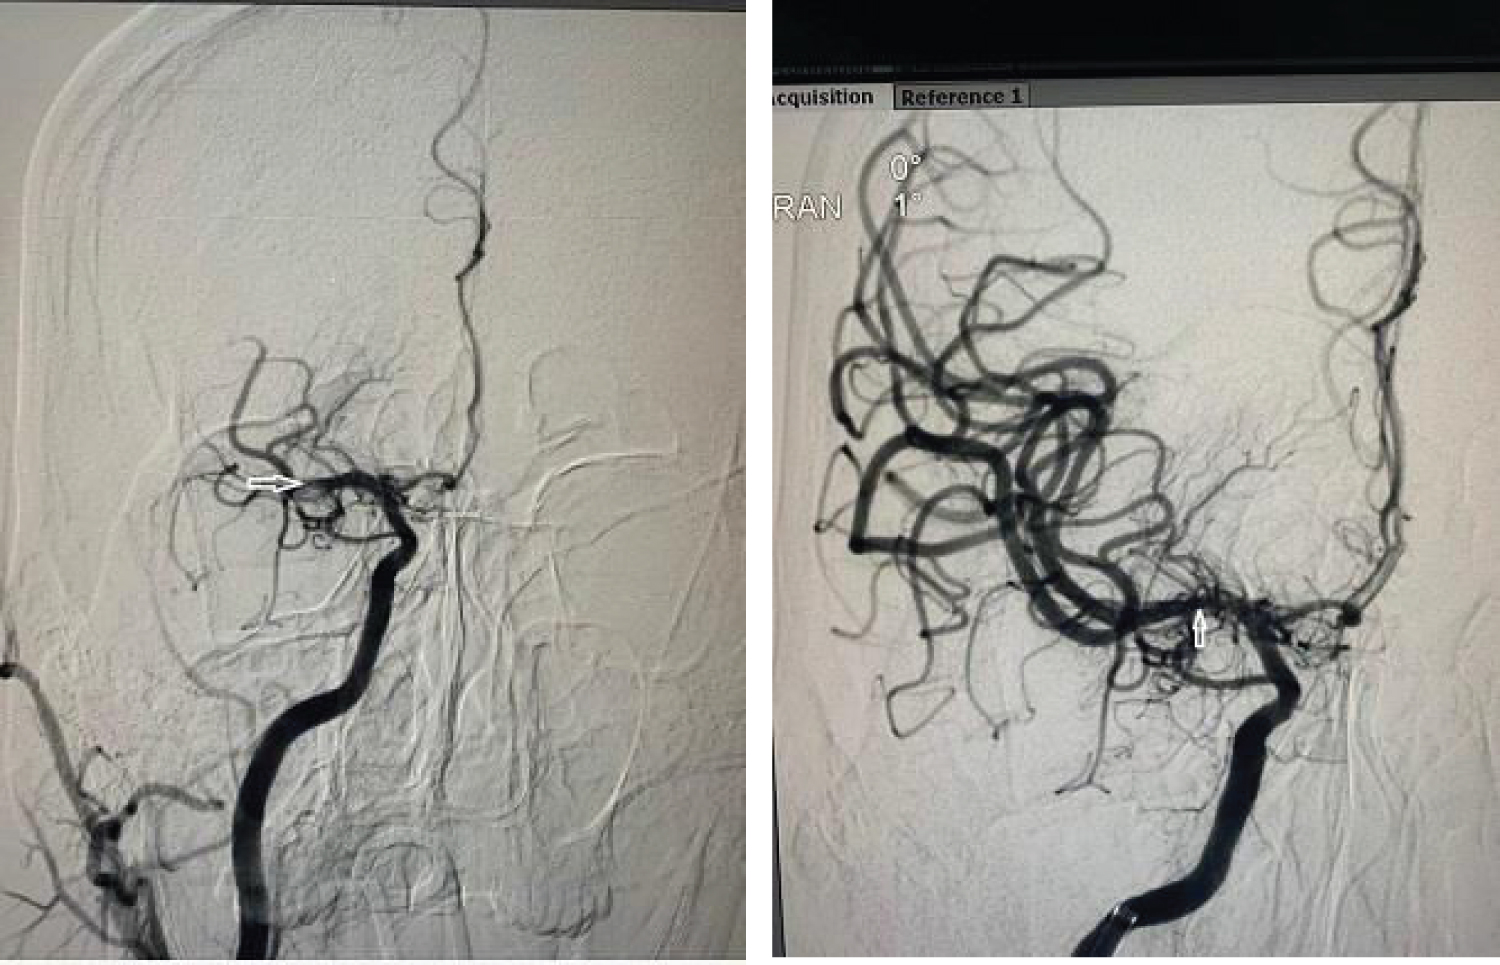

The subject was beyond the window period for intravenous thrombolysis, however in view of LVO and diffusion Flair mismatch, he was a candidate for mechanical thrombectomy. He underwent mechanical thrombectomy soon after and had complete reperfusion of the right MCA. He was noted to have hemorrhagic transformation of the right MCA infarct post mechanical thrombectomy on the CT scans of the head done hours after post thrombectomy as well as on day three post stroke. He was however continued on aspirin 100 mg once daily. He was started on mannitol 20% for brain edema. Clinically he continued to improve. On day six post stroke on examination he had only mild left facial weakness with power in the left limbs improved to MRC grade 4/5 in the left upper limb and 5/5 in the left lower limb. He was walking independently.

Figure 3: Pre and post mechanical thrombectomy DSA shows occluded and opened up Right MCA respectively. View Figure Chart 3